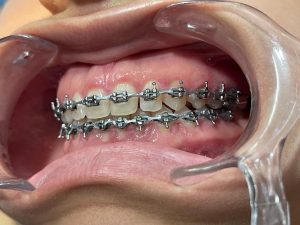

Tratamientos Ortodoncia Blanqueamiento dental Zoom Contacto 72 2795 9597 Marcar Ahora Envia whatsapp Visita nuestro facebook